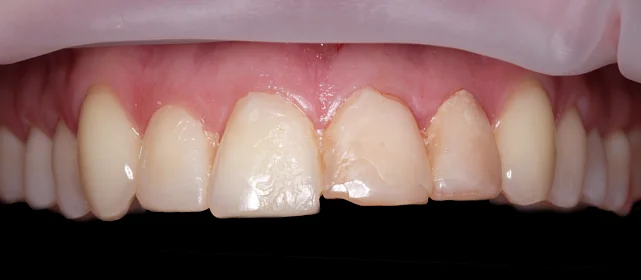

Зубы выровнены, смыкание нормализовано. Установлены несъёмные ретейнеры на обе челюсти, сняты сканы для ретенционных кап.

Решение: Поставили прозрачные элайнеры Click — начали с компактного набора из 20 кап. Основной комплект сделал основной объем работы, но для финальной доводки понадобился дополнительный набор из 10 кап. Итого 30 кап за 23 месяца. Результат — зубы на месте, смыкание в норме. Зафиксировали ретейнеры на обе челюсти, сняли сканы для ретенционных кап.